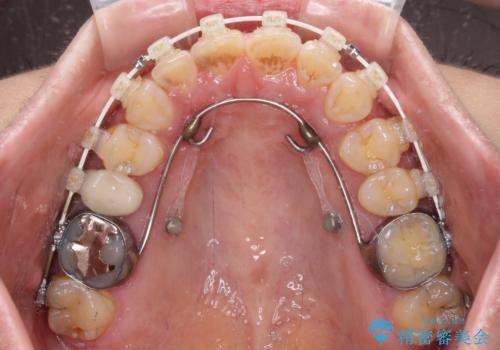

- 飛び出た上の前歯を気にして来院された患者様です。

奥歯の咬み合わせは、上顎歯列が理想的な一よりも数mm前方にある状態でした。

なるべく早めに治療を終えたいとのことで、補助装置を用いて上顎臼歯を後方に移動させ、同時にワイヤー装置にて整えることとしました。

舌の突出癖が原因で上下の歯に大きなスペースが生じていたため、舌のトレーニングをしっかり行っていただくことで、上顎歯列をスムーズに移動させることができました。